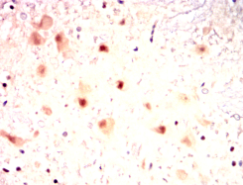

IHC    1/100 - 1/500